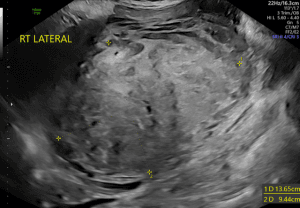

After repeated intravenous fluid boluses totaling 2000 ml of volume resuscitation, the anesthesiologist performed a FASO examination with the patient in supine position using a convex-array transducer. First, the right upper quadrant was examined, evaluating for free fluid in Morison’s pouch. Next, the left upper quadrant (splenorenal recess) was examined, followed by the suprapubic evaluation of the lower abdominal wall and the pouch of Douglas. The FASO examination found a large amount of free fluid in the abdominal cavity, mainly located in the hepatorenal recess and the pouch of Douglas.

FASO examination in our patient showed free fluid in all the abdominal windows. This finding, in the clinical context of hemodynamic instability was highly suggestive of intra-abdominal hemorrhage. FASO proved helpful in the clinical decision-making process to proceed with surgical intervention.